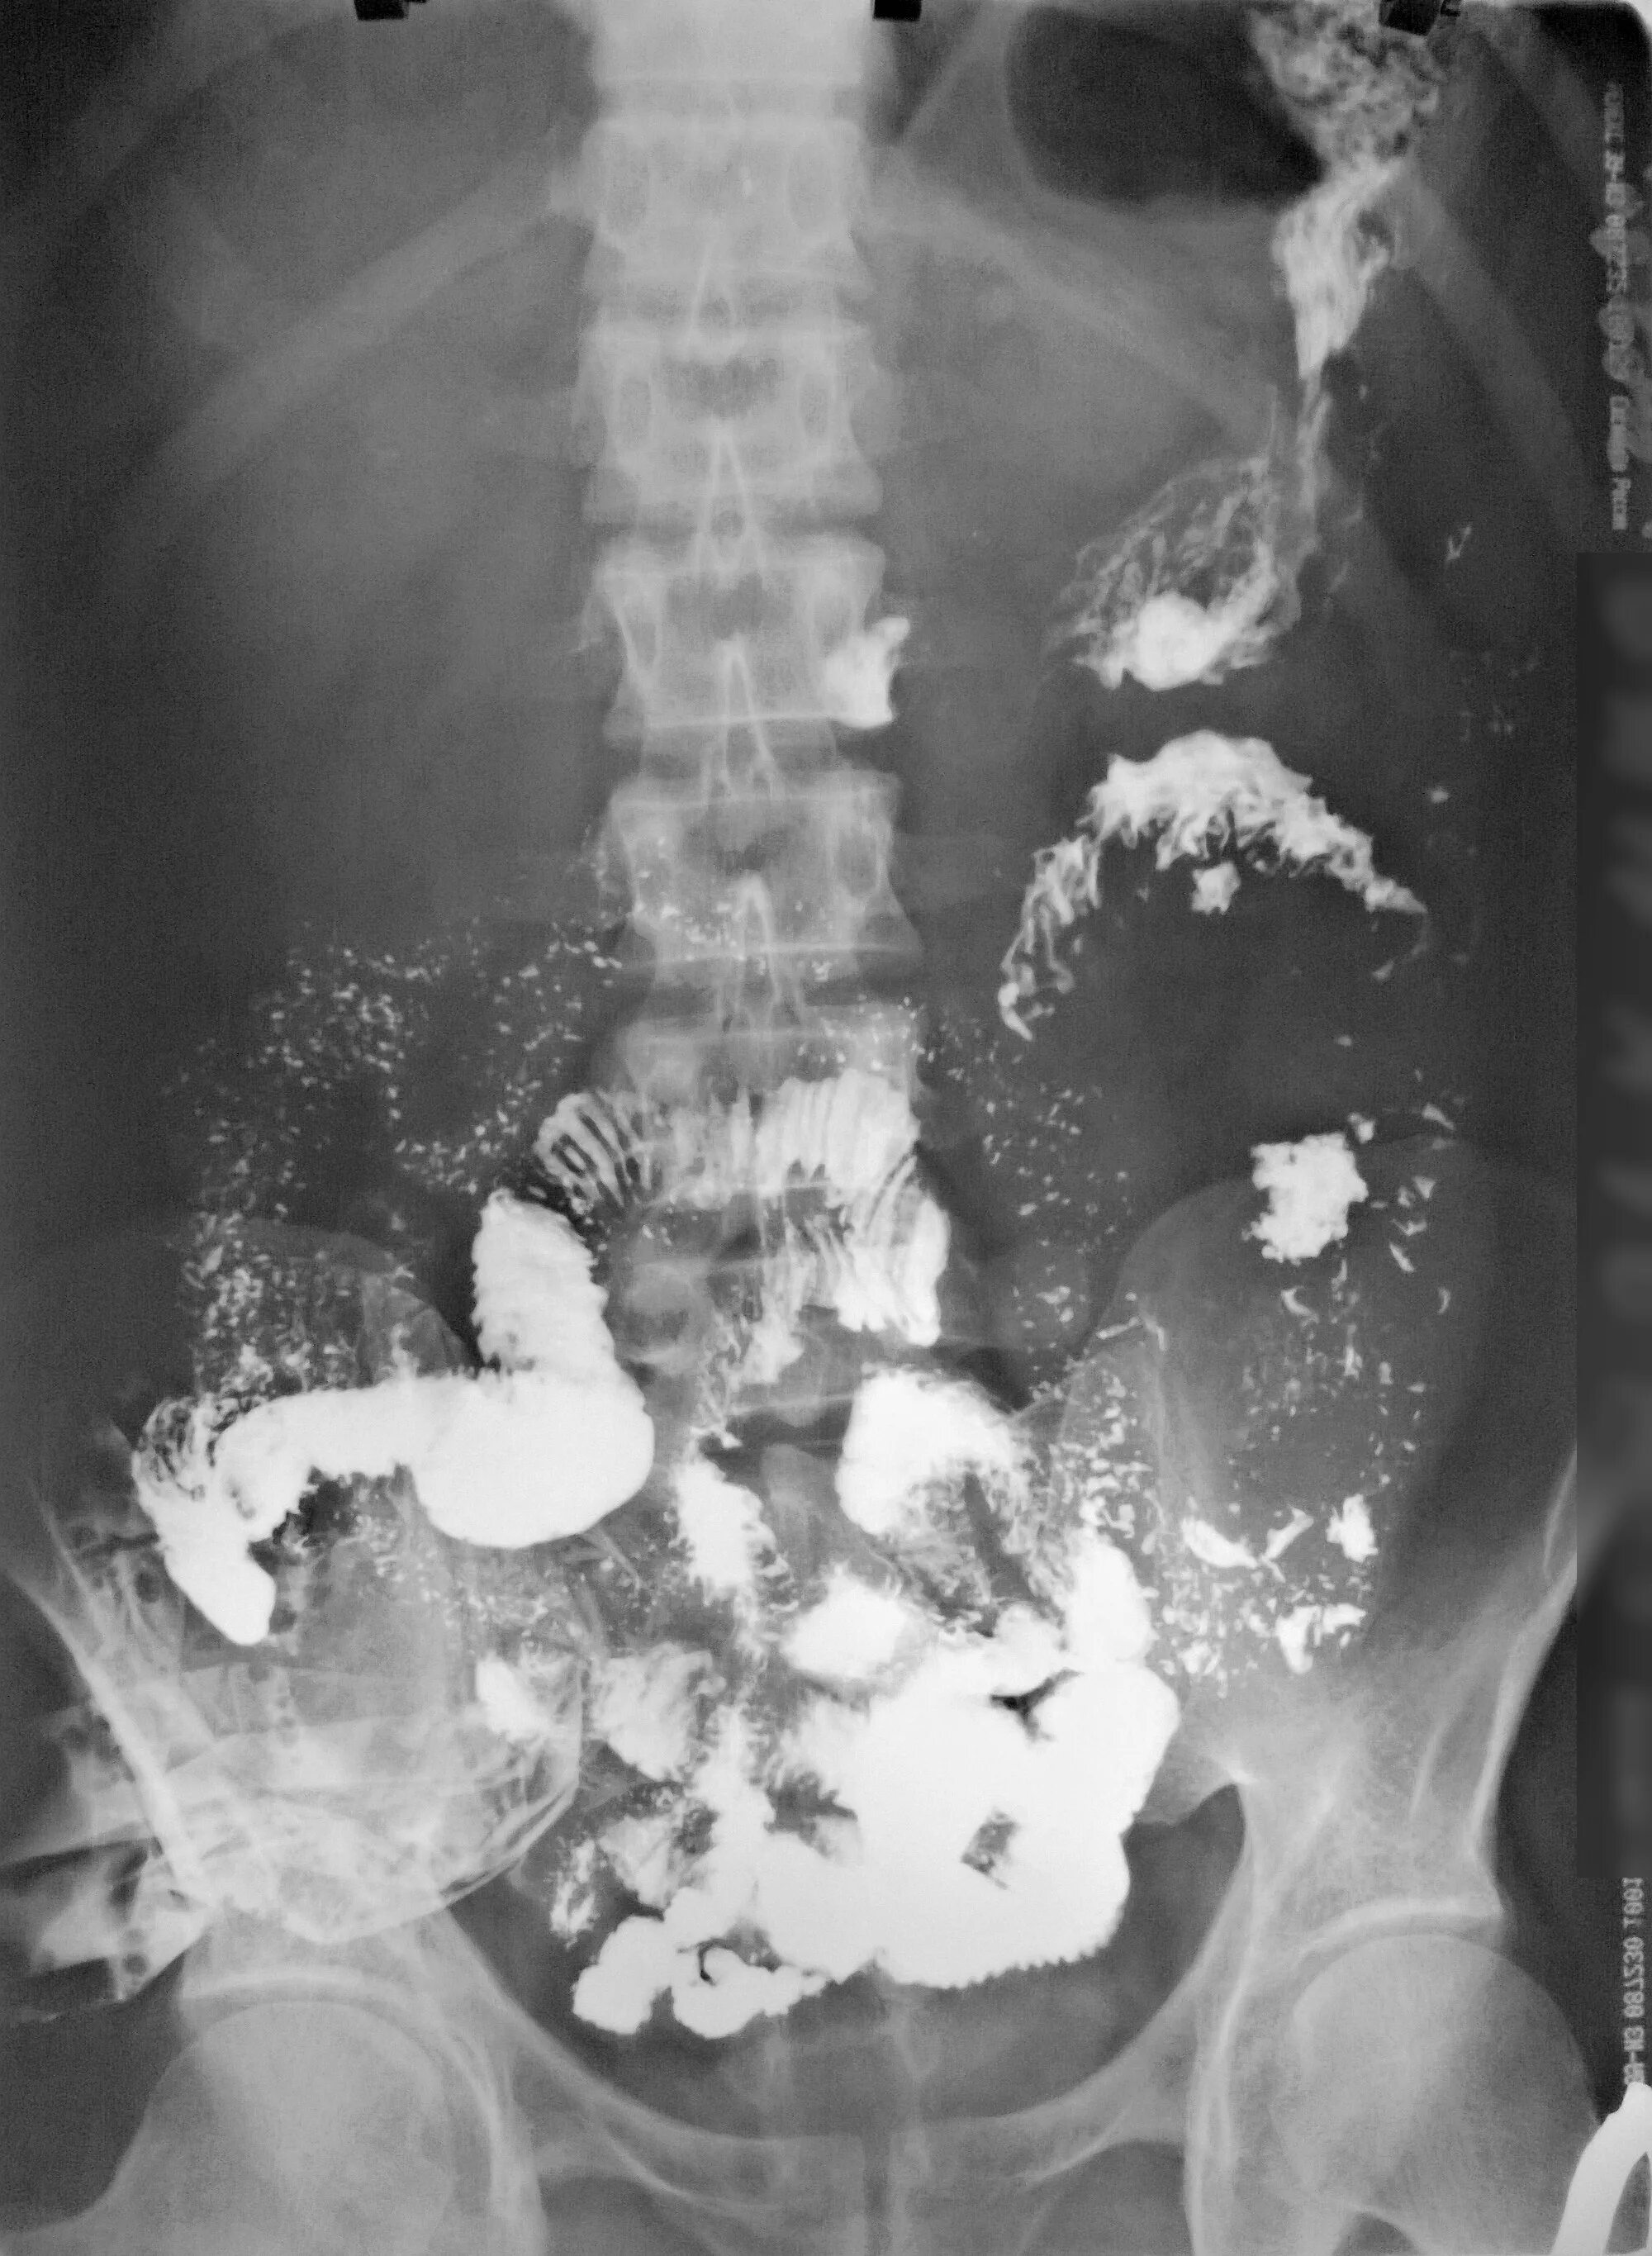

Пассаж кишечника